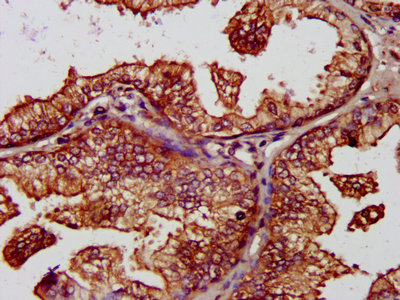

IHC image of CSB-PA03425A0Rb diluted at 1:1200 and staining in paraffin-embedded human prostate cancer performed on a Leica BondTM system. After dewaxing and hydration, antigen retrieval was mediated by high pressure in a citrate buffer (pH 6.0). Section was blocked with 10% normal goat serum 30min at RT. Then primary antibody (1% BSA) was incubated at 4°C overnight. The primary is detected by a biotinylated secondary antibody and visualized using an HRP conjugated SP system.